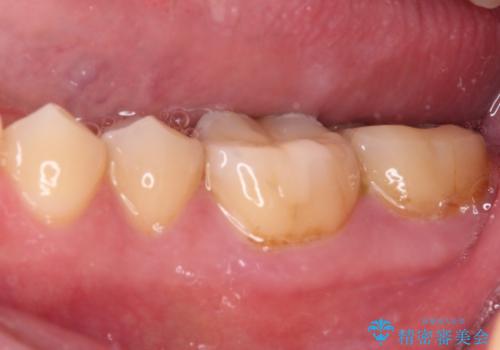

- 左右下顎の奥歯に違和感を感じるとのことで来院された患者様です。

最近ものが挟まりやすくなったり、冷たいものがしみるようになったりと言った症状があり、診査したところ、歯質の欠損や不適修復物などが認められました。

精度の高いセラミックインレーによる修復治療が第一選択となりますが、一方の歯は元々修復物が大きく、咬合力の強い方であったので、セラミッククラウンによる補綴治療を行うこととしました。